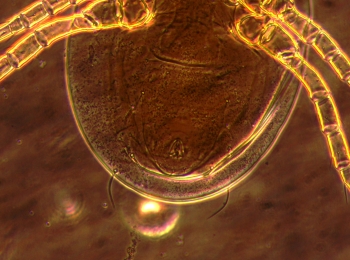

以下图片是医生在生物显微镜下发现他的睫毛根部居然有螨虫在蠕动。看到显示屏上蠕动的虫体时,着实吓了一跳。

螨虫体型细小,在显微镜下是半透明的,普通生物显微镜很难看清楚,明美倒置显微镜MI52-N支持相衬观察,能让螨虫轮廓和细节更清晰地呈现出来。

明美倒置显微镜下捕捉下尘螨